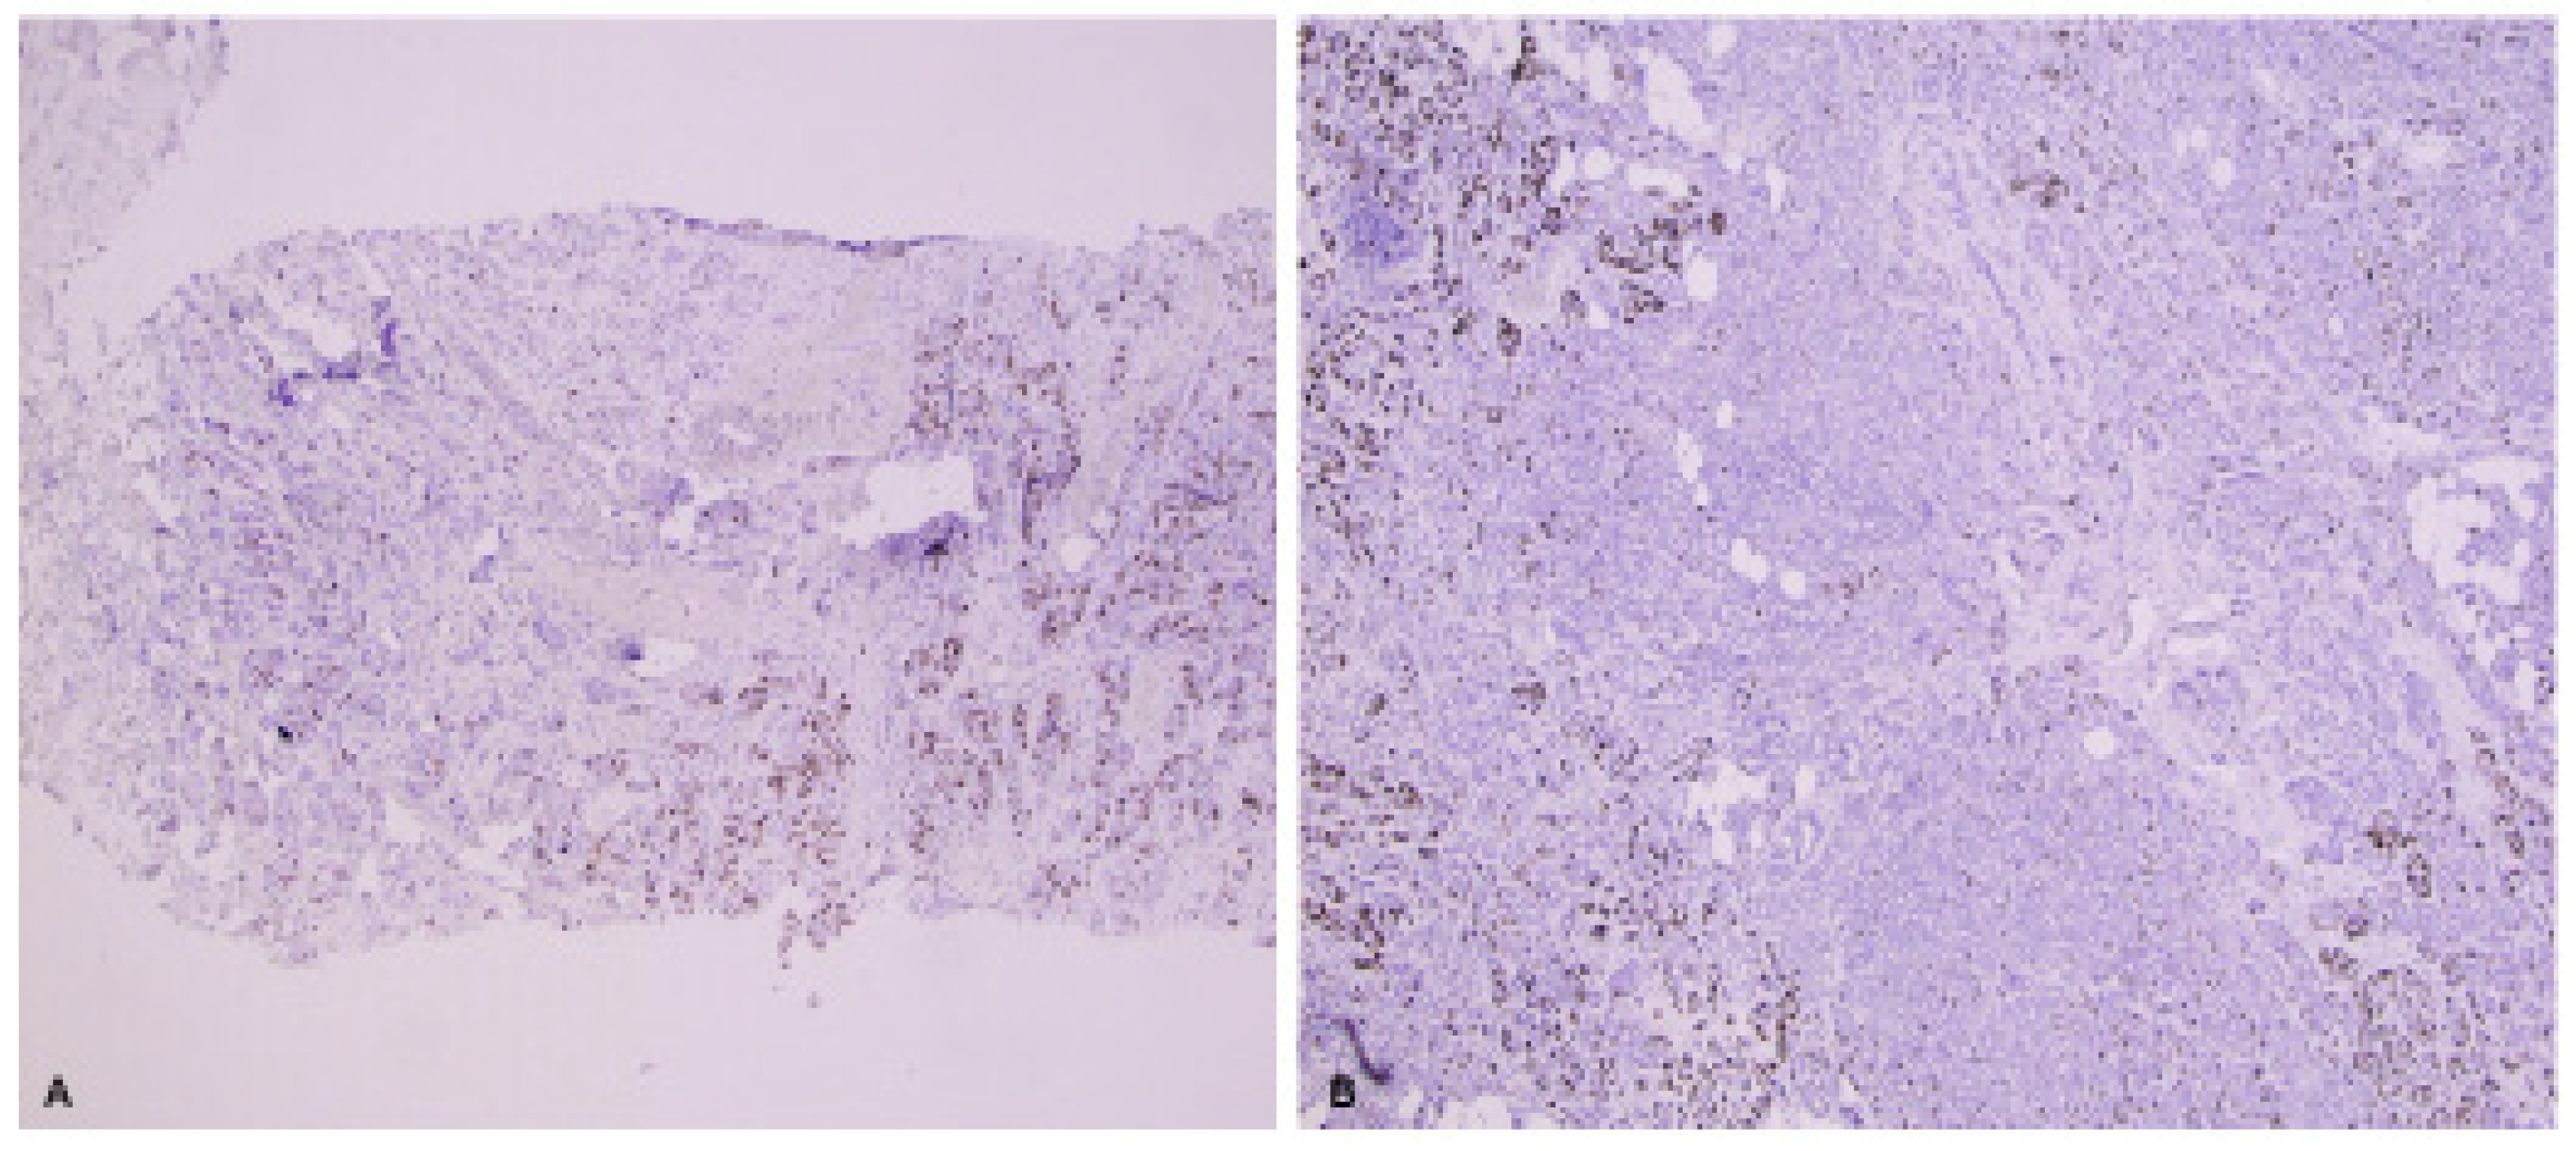

| Method | Yes | Calculate the percentage of positive invasive carcinoma cells by counting all positive and negative invasive carcinoma cells within the examined region of the slide. Do not consider intensity. |

| Region of Slide | No | A global counting method appears to have higher reproducibility than a hot spot counting method. |

| Digital Imaging | No | Evidence to date suggests that automated scoring is not worse than standardized visual scoring for core-cut biopsies. |